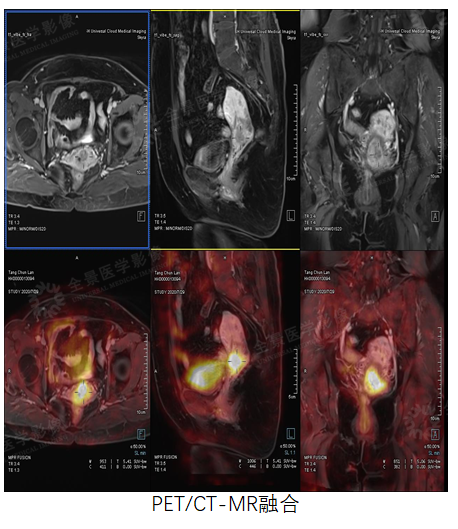

妇科

案例1 :女性,46岁,下腹部不适1周,CA125:791 u/ml↑。

PET/CT示盆腔内占位,由于PET/CT软组织分辨率有限,无法准确定位。MR增强示双侧卵巢显示不清,盆腔占位,考虑卵巢来源,性质待定。

PET/CT-MR融合,综合二者信息,考虑卵巢来源的恶性肿瘤。

术后病理:卵巢高分化浆液性癌